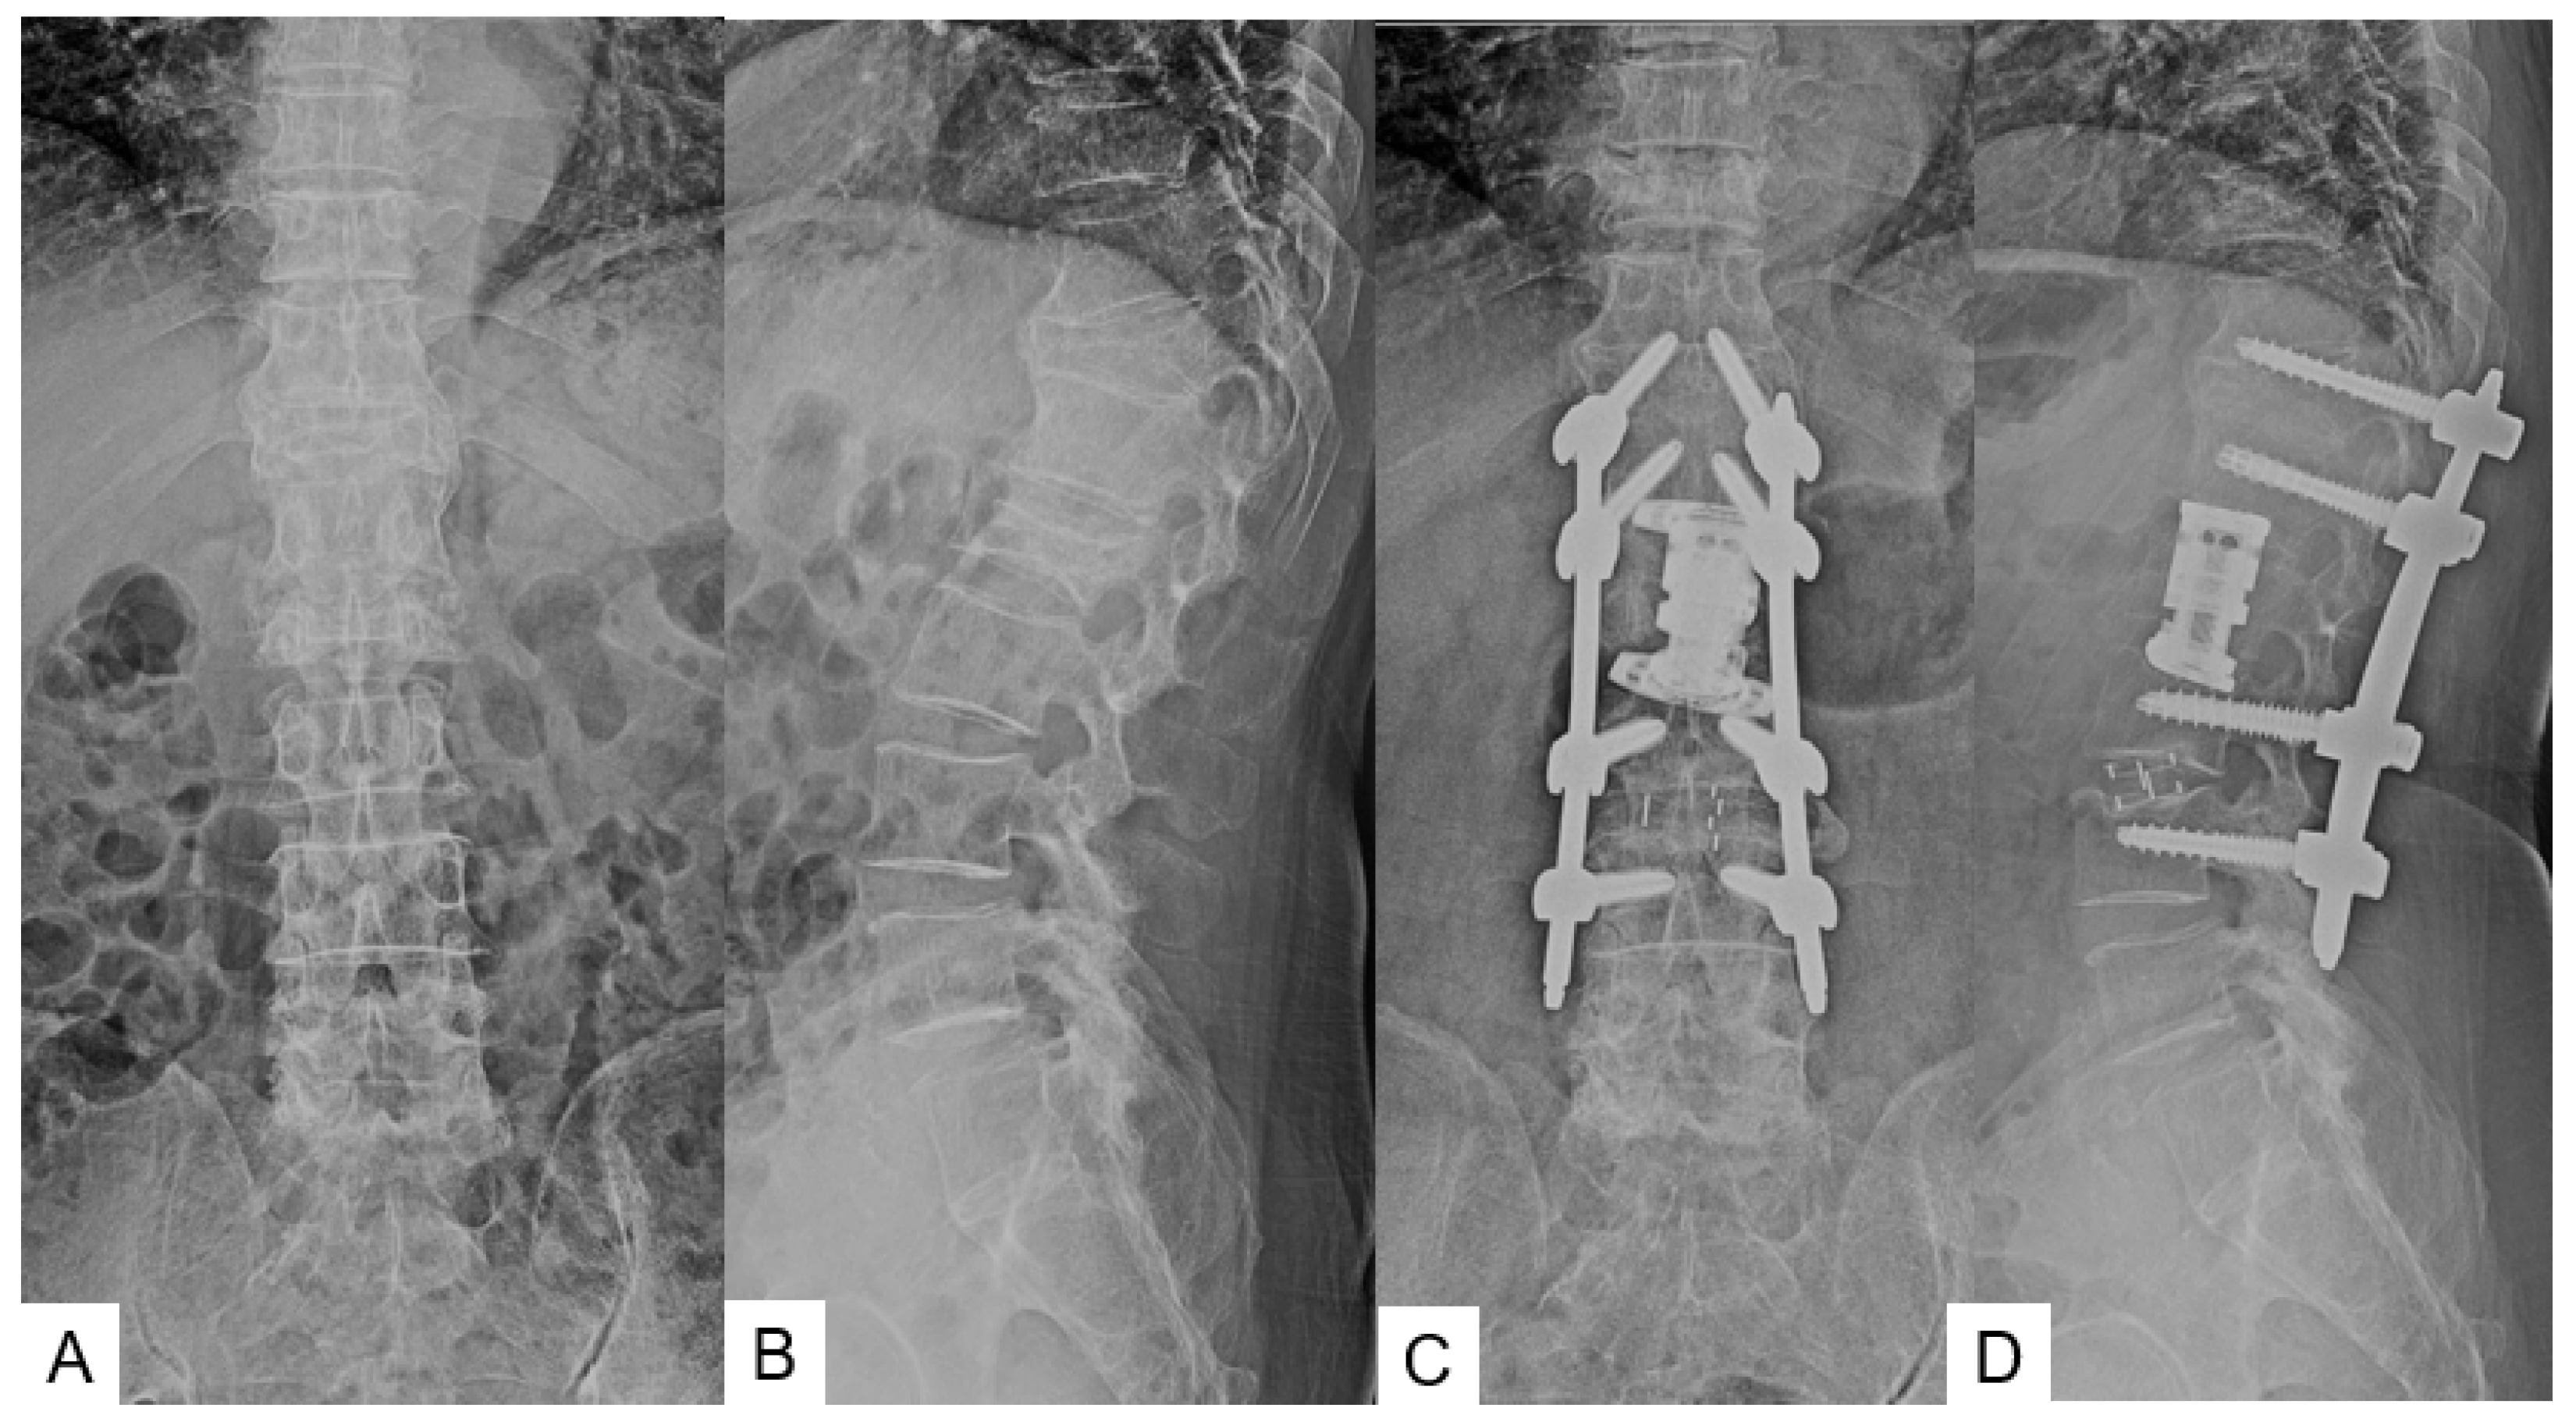

3.1. Clinical Evaluation

3.2. Radiographic Evaluation